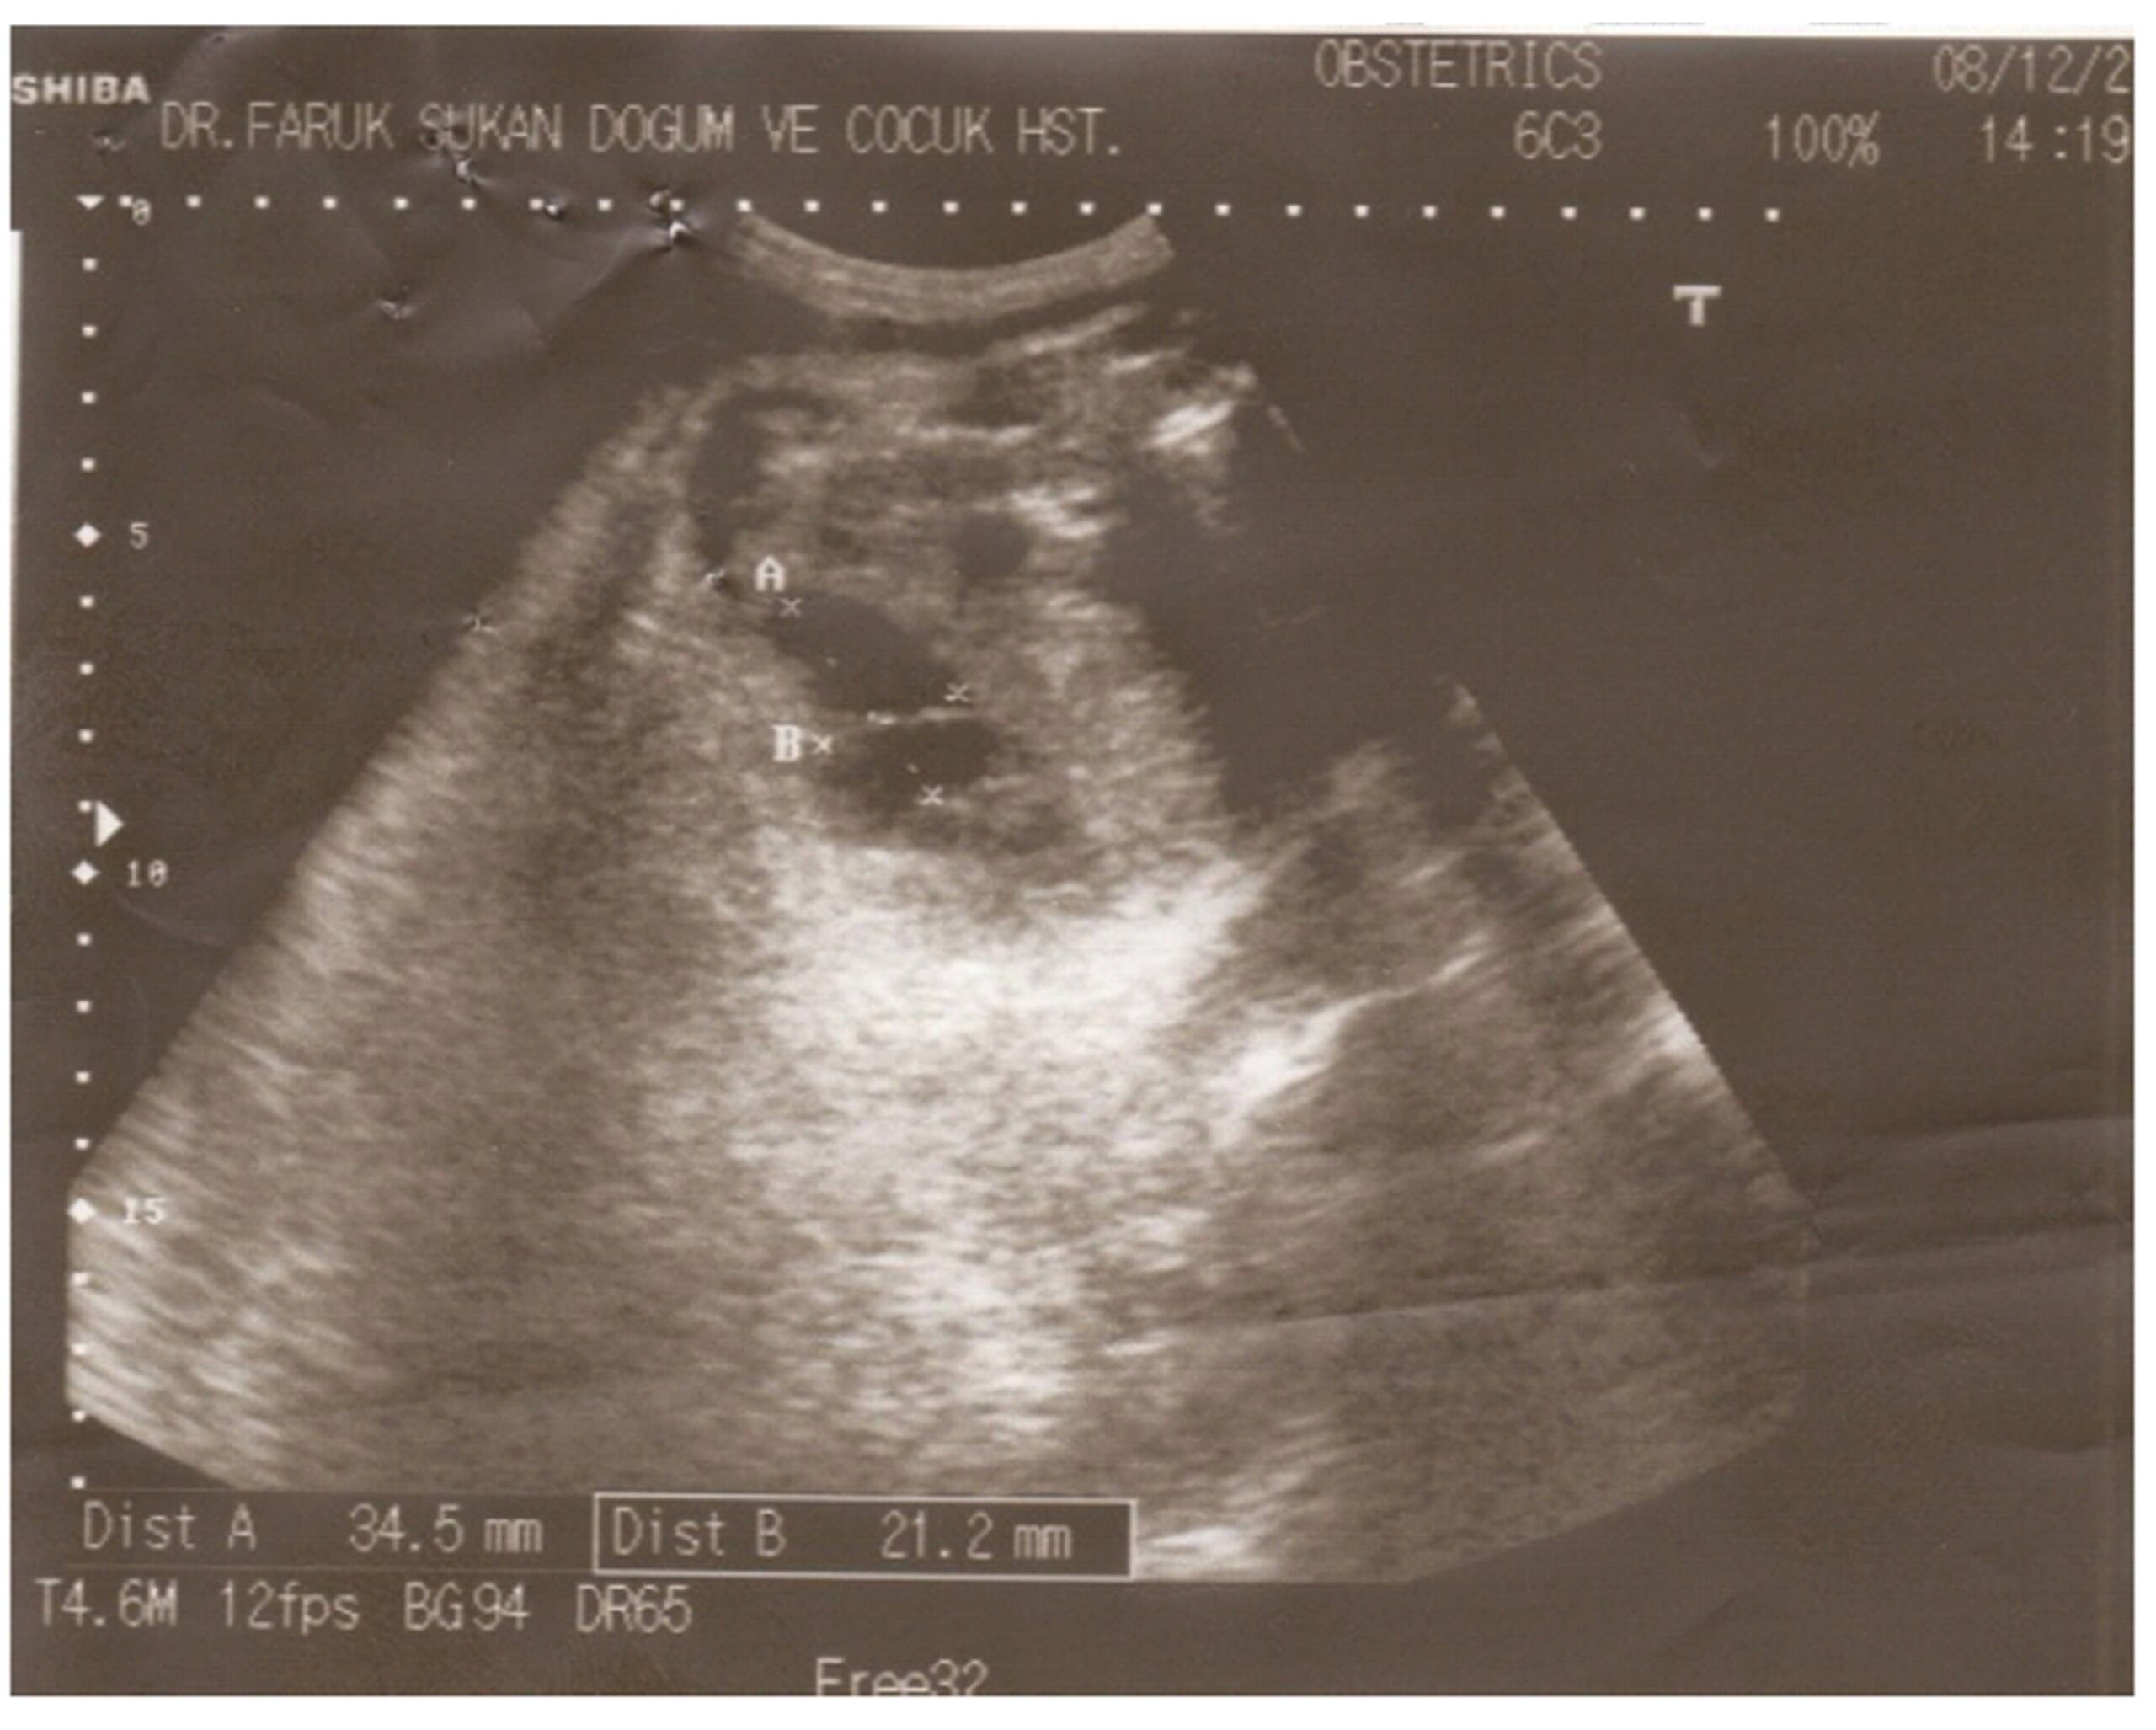

A 31-year old woman, having given birth by caesarean section two times before, admitted to our hospital for control in the 34th week of her 3rd pregnancy. In maternal ultrasonography, thin walled homogeneous cystic masses with smooth-bordered were found within the pelvis of fetus. The largest one was 3.5 cm diameter (Fig 1).  The family was informed of the fact that the infant would be evaluated by a pediatric surgeon after birth and if required, it might be operated. At the end of the pregnancy term, the mother underwent a cesarean section, and a female baby weighing 2700 grams was born. All the physical examination findings of the baby, including abdominal palpation, were normal. All routine blood tests were normal. As a result of abdominal CT, radiologists reported as cystic lesion of 4.5×2 cm which have thin walled and septas in places. In abdominal ultrasonography, again multiple cysts were observed. After the required preparations for the operation were completed, the newborn was operated in the third day after birth in order to prevent serious complications to be caused by cysts. Under endotracheal general anesthesia, diagnostic laparoscopy was performed through telescope of 5 mm 0 degree via a trocar inserted from the umbilical region.  As many cysts had been observed in the mesentery of the ileum, laparotomy was performed as resection and anastomosis was required. During the laparotomy, multiple cysts, the biggest were 4 and 3 cm, located in the mesentery of the distal ileum, were seen (Fig 2).  The cysts together with 10 cm of ileum was resected, and end-to-end anastomosis was performed. The postoperative period was uneventful, and the newborn was discharged from the hospital on the postoperative 7th day.  In Gross Pathological Examination, a number of yellow thin walled cysts varying between 0.3 and 4 cm from which strained looking yellowish liquid is discharged were observed in the mesentery of 10 cm-ileum. In microscopic pathological examination, lymphatic veins, congested vein sections, mononuclear cell infiltration consisting focuses in places were observed in fibro-muscular wall of cystic structure covered by endothelium. Diagnosis was reported as mesenteric cystic lymphangioma. Due to the recurrent nature of mesenteric lymphangiomas, the patient was followed at between six month intervals evaluating for her general status and physical development. Abdominal US scan was performed at every visit. Now, she is three years old and is doing well without any abdominal complaints.

Figure 1: In maternal USG taken in the 35th week of pregnancy, cystic lesions are seen in the pelvis of fetus, the biggest ones of which are 34.5 and 21.2 mm